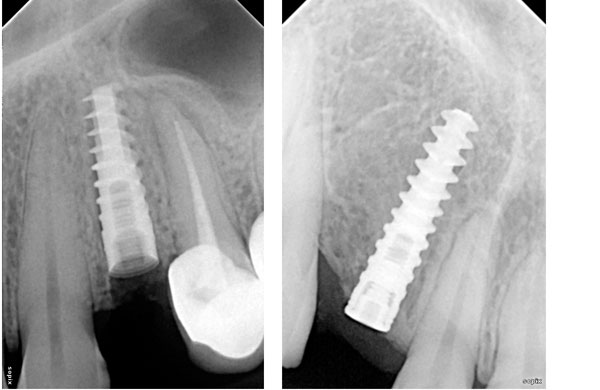

A dental implant is a titanium post that is surgically positioned into the jawbone beneath the gum line that allows your dentist to mount replacement teeth or a bridge into that area. An implant doesn't come loose like a denture can. Dental implants also benefit general oral health because they do not have to be anchored to other teeth, like bridges.

Types of Placed

• Immediate placement

• Delayed loading